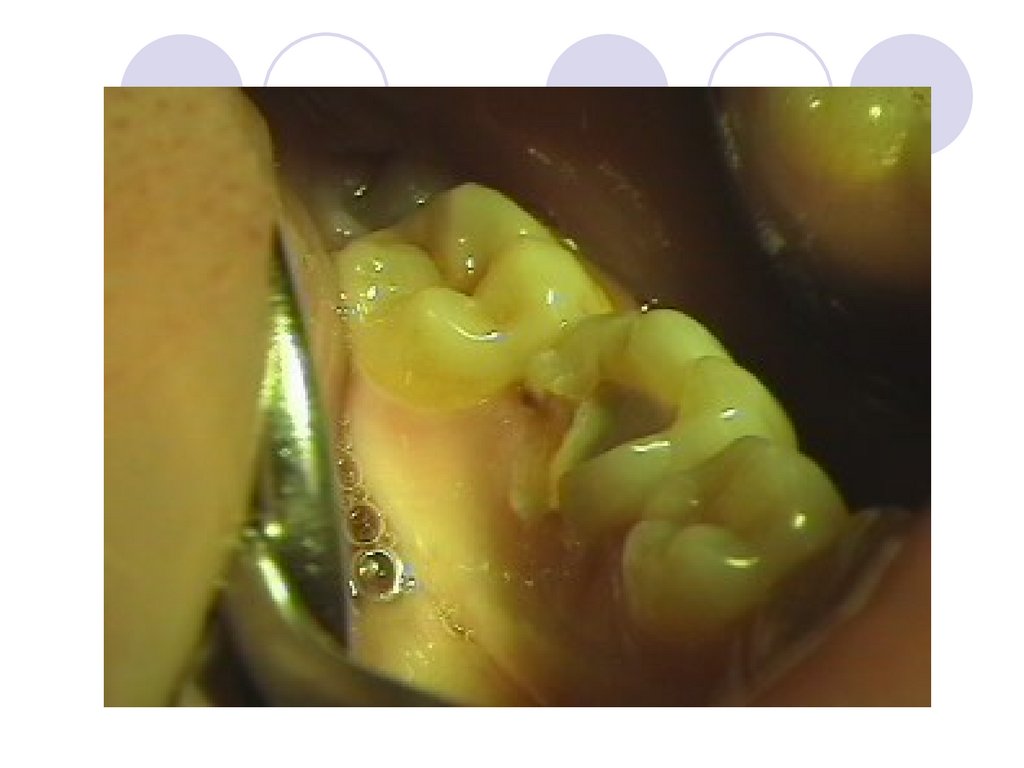

Прежде чем приступить к подготовке

полости для вкладки, надо удалить из

нее размягченный дентин. Затем

переходят к формированию основной, а

в случае необходимости и

дополнительной полости.